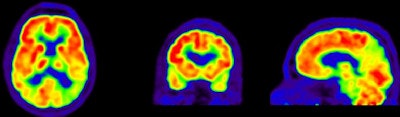

Researchers then proceeded to the PET scans. First, patients were imaged with PiB for 90 minutes to obtain parametric images of the biomarker binding to potential clusters of amyloid. FDG-PET scans were then conducted 45 to 60 minutes after injection and lasted for 15 minutes. Standardized uptake value (SUV) ratios were calculated throughout the brain.

The resulting PET images were visually assessed by a nuclear medicine physician and reported to the neurologists to determine how the additional information changed their initial clinical diagnoses and their confidence in those interpretations.

PiB-PET scans were positive in 40 (61%) of 66 patients with clinical Alzheimer's and in five (28%) of 18 patients with clinical frontotemporal dementia. FDG SUV patterns matched the clinical diagnosis in 58% of patients with Alzheimer's and 33% of patients with clinical frontotemporal dementia, the authors noted.